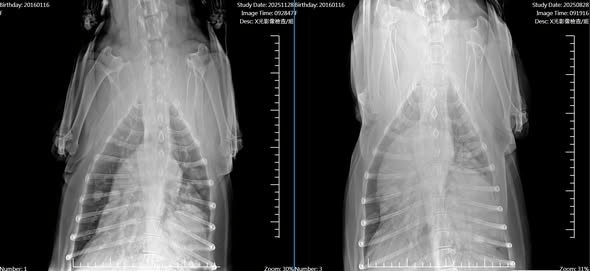

X 光影像對比:眼見為憑的進步

經過三個月的積極治療,寶貝回診拍攝追蹤 X 光。影像結果讓診間的所有人都鬆了一口氣!

【腹背視角對比】

治療前(右圖): 右側肺葉(畫面左半邊)幾乎呈現「白茫茫」的一片,正常的肺紋理完全消失。

治療三個月後(左圖): 影像上的白色實質化區域大幅消退,腫瘤體積明顯收縮,顯示藥物控制效果非常理想。

【側面視角對比】

治療前(右圖): 肺後葉區域可見大面積、邊緣模糊的白色團塊,顯示腫瘤組織嚴重浸潤,肺部透氣空間極少。

治療三個月後(左圖): 白色團塊的密度明顯變淡,範圍顯著縮小!原本被遮蔽的黑色區域(代表充滿空氣的健康肺部)重新出現了。